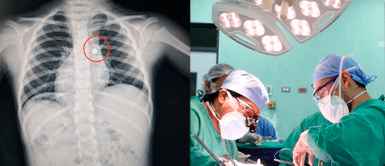

Médicos especialistas del Hospital Víctor Lazarte Echegaray, de la Red Asistencial La Libertad, salvaron la vida de un niño de cuatro años de edad, quien presentaba dificultad a la hora de respirar por tener alojada una pila en el pulmón derecho.

Apenas llegó al establecimiento de EsSalud, los médicos neumólogos le realizaron diversos exámenes, como radiografía y tomografía, que revelaron que el menor tenía, en el bronquio del pulmón derecho, una pila de reloj de 8mm.

“Tenía una pila en el bronquio derecho; por ello, fue llevado a sala de operaciones, donde le realizamos la extracción del cuerpo extraño y la limpieza del líquido del ácido que dejó esta batería en el bronquio”, subrayó.

El médico indicó que, a través del procedimiento denominado video broncoscopia, se extrajo la pila de reloj.